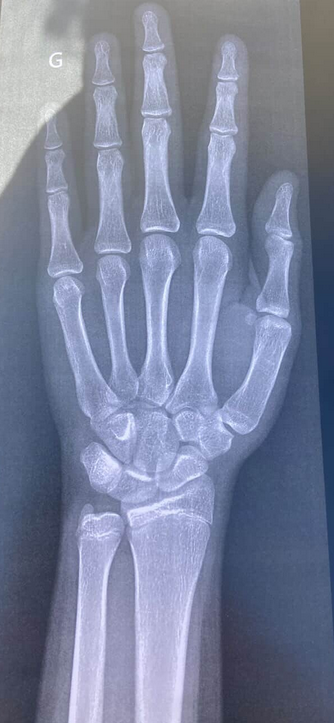

almost closed or even alrim worried, bone age is 16 and i'm 16

u think i can get 5 cm ?almost closed or even alr

i give 2-3 max but nobody can predict bro , but they are almost closed so it means ur growth is almost over u will prob even get lessu think i can get 5 cm ?